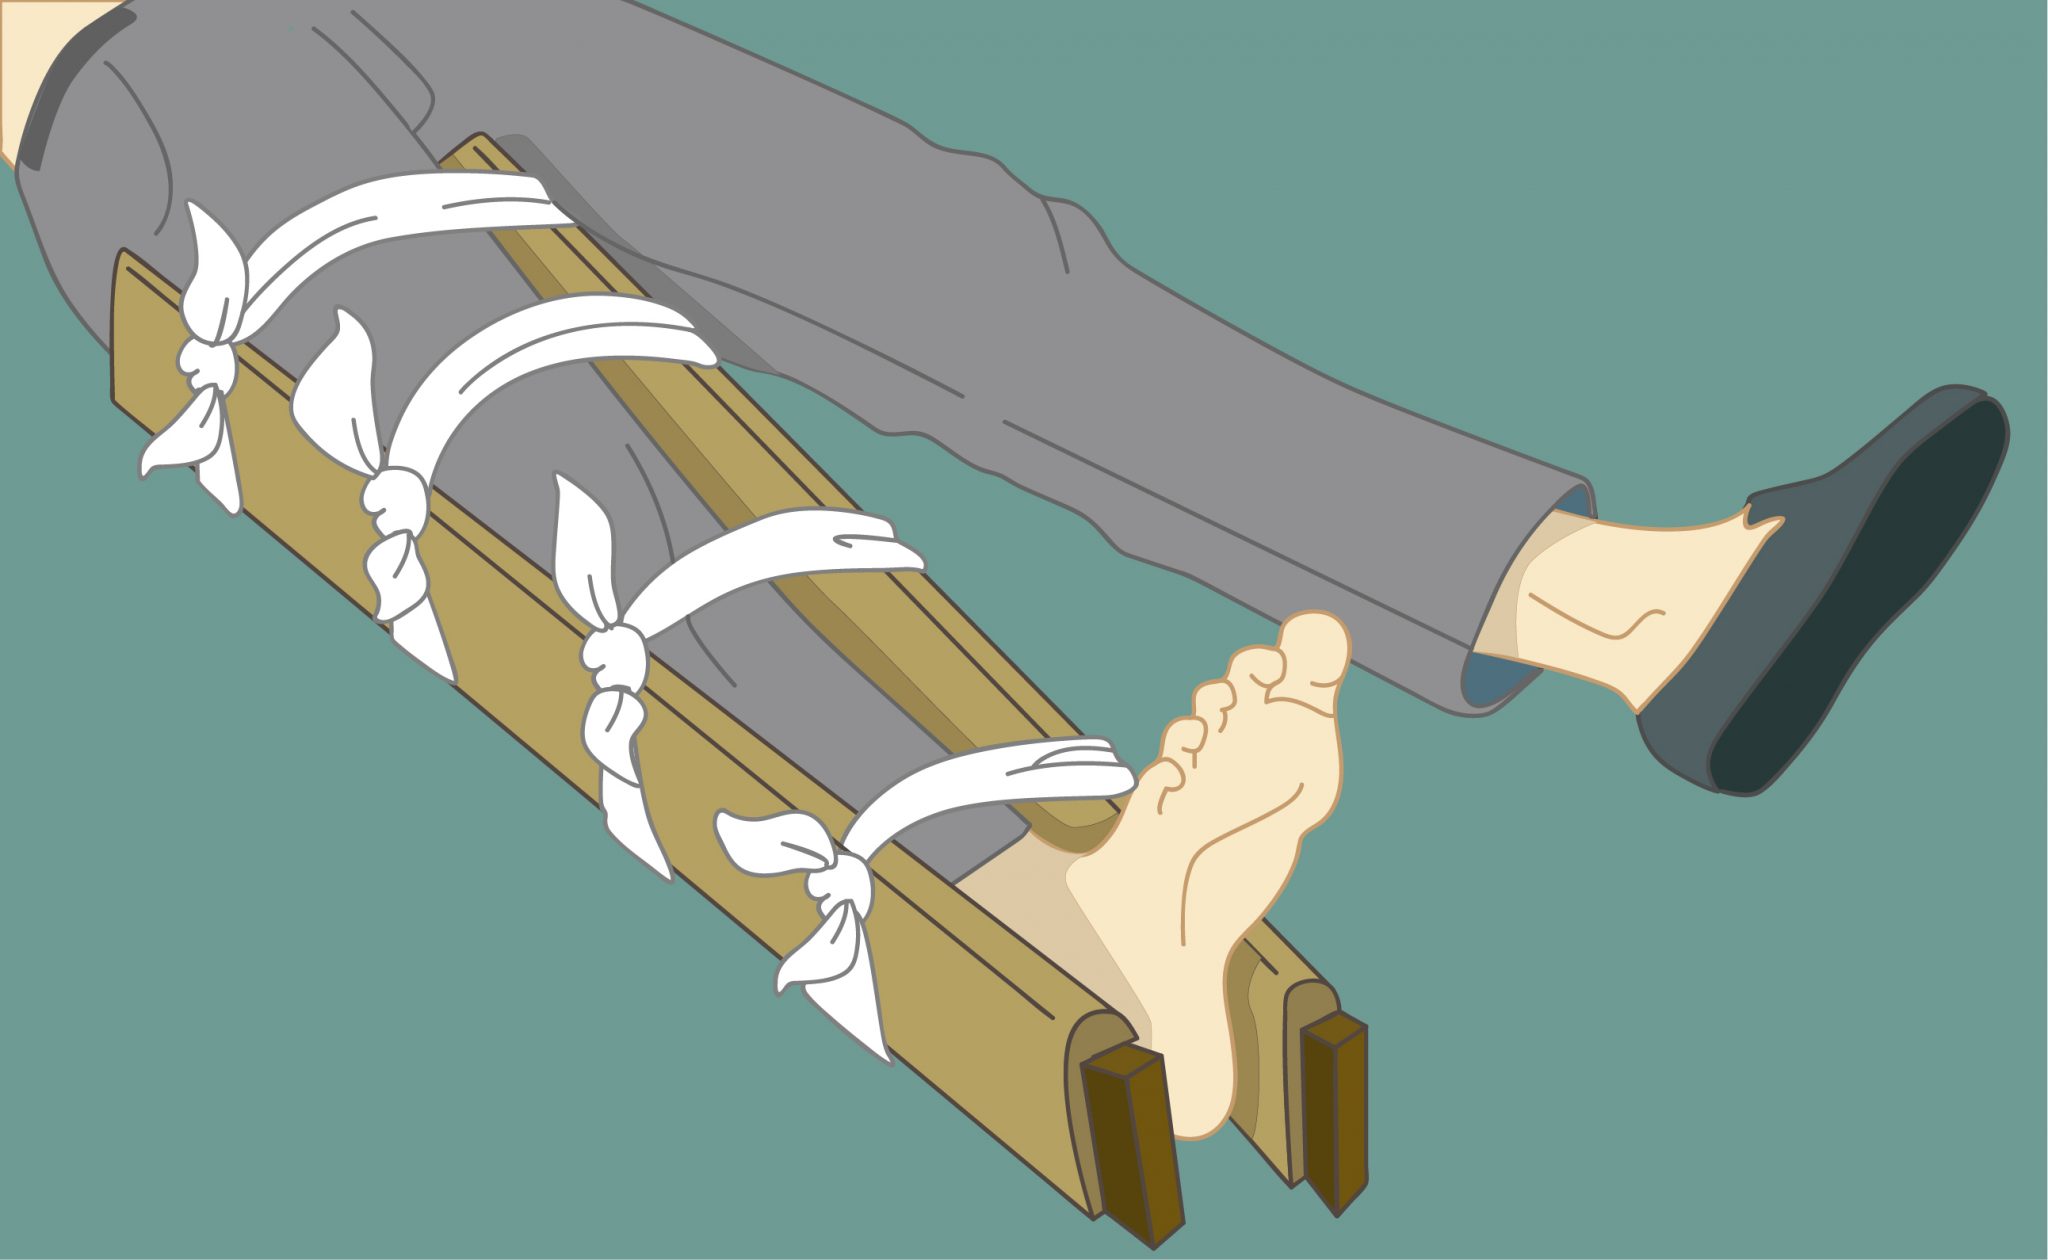

Опытные и квалифицированные специалисты современного реабилитационного центра «Исток» в Беслане проводят для всех своих пациентов качественное восстановление после такого опасного повреждения с применением персонального подхода при подборе оптимальных методов воздействия. Начинать такие мероприятия следует уже на 2-3 день после получения травмы после установки гипса и фиксации конечности. Благодаря таким мероприятиям, удаётся достигать скорейшего выздоровления и минимизации последующих осложнений. В противном случае пренебрежение реабилитационной программой может привести к развитию артроза, артрита, прогрессировании остеохондроза, нарушению симметрии тела и прочему.

Опытные и квалифицированные специалисты современного реабилитационного центра «Исток» в Беслане проводят для всех своих пациентов качественное восстановление после такого опасного повреждения с применением персонального подхода при подборе оптимальных методов воздействия. Начинать такие мероприятия следует уже на 2-3 день после получения травмы после установки гипса и фиксации конечности. Благодаря таким мероприятиям, удаётся достигать скорейшего выздоровления и минимизации последующих осложнений. В противном случае пренебрежение реабилитационной программой может привести к развитию артроза, артрита, прогрессировании остеохондроза, нарушению симметрии тела и прочему.

В каждом отдельном случае длительность осуществления восстановительных мероприятий будет формироваться персонально в соответствии со степенью тяжести перелома, особенности состояния человека и иными важными факторами. В среднем она может занимать от 1,5 месяцев до полугода.

При получении такой травмы больной становится ограниченным в своей двигательной активности, не может должным образом ухаживать за собой и вести домашнее хозяйство. И в соответствии с этим правильным решением будет выступать размещение больного на время восстановления в наш частный реабилитационный центр «Исток» в Беслане. Наши специалисты применяют ко всем пациентам персональный подход и подбирают только эффективные и проверенные методики и технологии воздействия.